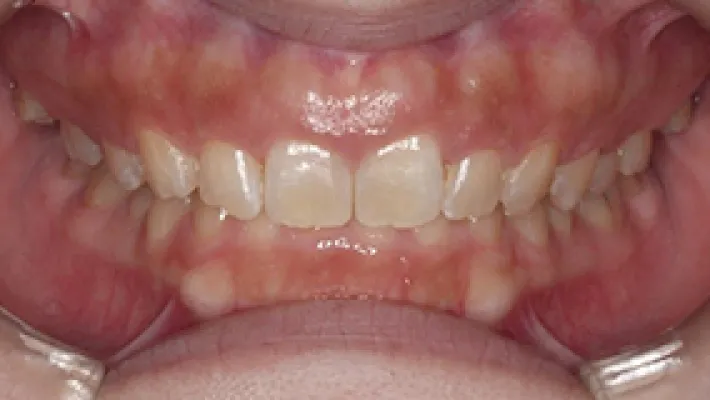

施術前

施術後

マウスピース矯正の部分矯正で上下前歯のすきっ歯を改善した症例です。

状態にもよりますが、すきっ歯はマウスピース矯正の得意とするケースの一つです。

効率的な治療計画で最小限の期間と負担で矯正を行いました。

矯正治療の期間・方法

矯正治療の期間や方法は歯並びや顎骨などの状態によって大きく異なります。

矯正治療は歯や歯周組織などに必ずダメージがあります。

矯正治療のダメージを最小限にするために健康的で現実的な治療計画を提案します。

治療費

583,000

治療期間

6.5ヶ月